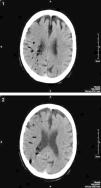

TC cráneal sin contraste realizada 6h después del procedimiento colangioendoscópico y el inicio de la sintomatología. Los cortes tomográficos realizados en ambos centros semiovales muestran la existencia de múltiples imágenes redondeadas de baja densidad compatibles con múltiples burbujas aéreas intraarteriales distribuidas a lo largo del territorio vascular de la arteria cerebral media derecha. Comienzan a observarse los signos precoces típicos de un accidente isquémico agudo con pérdida de la diferenciación corticosubcortical y tenue hipoatenuación del hemisferio cerebral derecho producidas por émbolos gaseosos.

Durante la dilatación, el paciente presenta una súbita disminución del estado de alerta con discreta desaturación, por lo que se detiene el procedimiento y se aplica oxígeno al 100% mediante mascarilla nasal. Ya en planta, el paciente se encuentra consciente y orientado, y tras la realización de una exploración neurológica básica se observa una disminución de la fuerza del hemicuerpo izquierdo. Ante la sospecha de ictus cerebral se solicita consulta urgente al Servicio de Neurología, que confirma estos hallazgos; éste, a su vez, solicita una TC urgente (figs. 3 y 4).

La TC urgente muestra la presencia de múltiples burbujas distribuidas a lo largo del territorio vascular de la arteria cerebral media derecha con pérdida de la diferenciación corticosubcortical e hipodensidad generalizada de todo el hemisferio derecho con respecto al lado contralateral compatible con externo infarto agudo de todo el territorio de la arteria cerebral media derecha secundario a múltiples émbolos gaseosos.